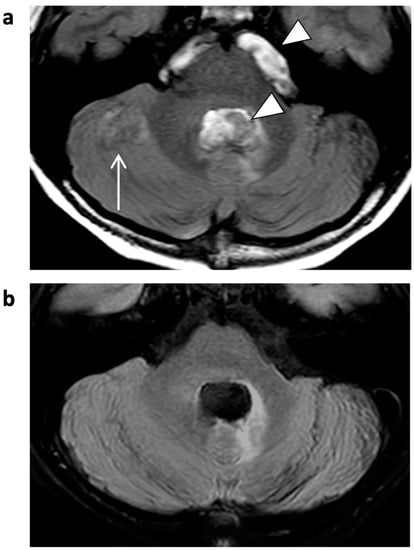

Figure 4.

Unenhanced 3D T1 TFE images of a 6-year-old male patient with astrocytoma (not shown). “Starry-sky” artifact presenting as subtle salt-and-pepper-like noisiness in central structures of the acquired volume in CS (b); not present in previous SENSE imaging (a). White circle indicates artifact.